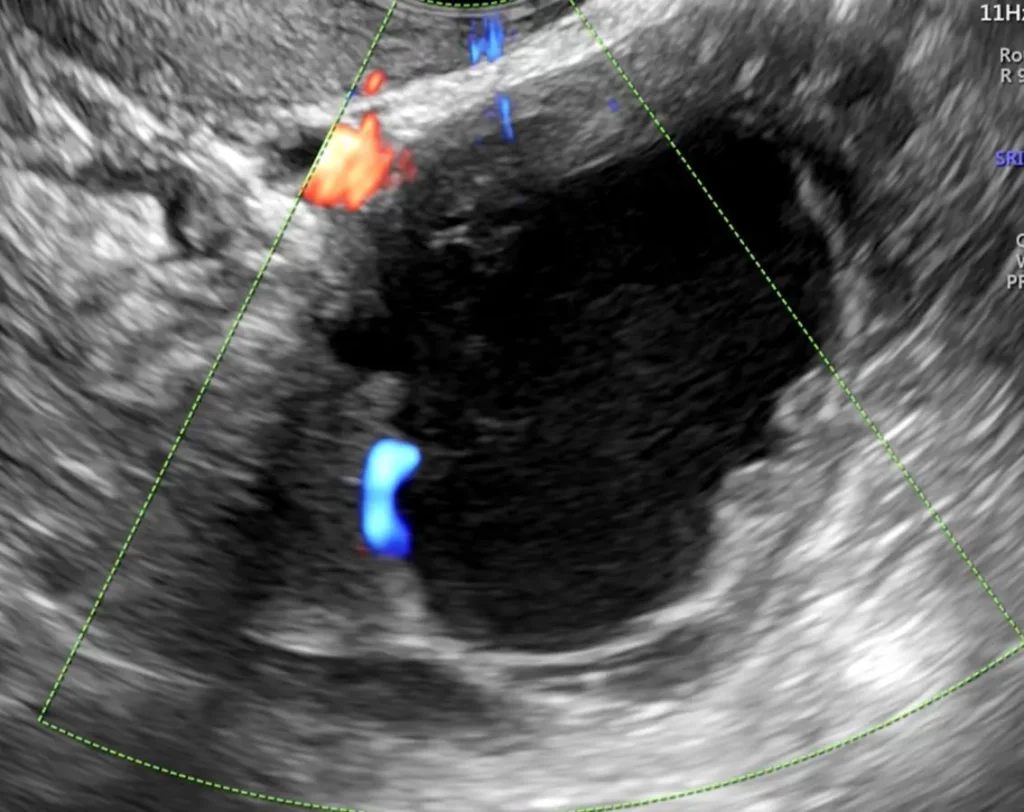

Si tratta di un esame ecografico dell’apparato genitale femminile interno (utero e annessi ovvero tube e ovaie).

- Ecografia trans-vaginale: esame effettuato dopo svuotamento della vescica introducendo una sonda all’interno della vagina coperta da un guanto o un involucro apposito monouso. Essa rappresenta la modalità di effettuazione più indicata nella maggior parte delle condizioni cliniche.